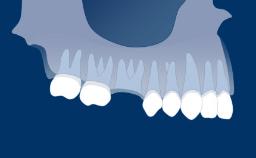

Introduction to Implant Dentistry

Timing of Implant Placement after Tooth Extraction

Learning Module